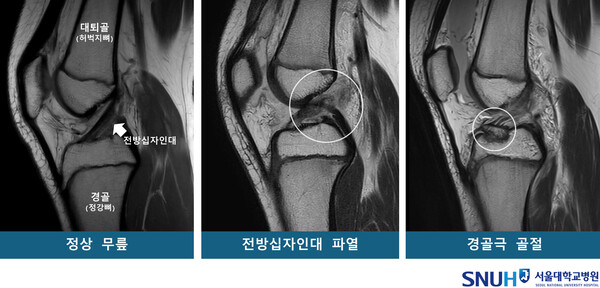

소아청소년은 뼈와 인대, 근육이 완전히 성숙하지 않아 스포츠 활동 중 무릎 부상에 특히 취약하다. 대표적인 무릎 손상으로는 ‘전방십자인대 파열’과 ‘경골극 골절’이 있으며, 겉보기에는 비슷한 사고 상황에서도 어떤 아이는 인대가 끊기고, 다른 아이는 뼈가 부러지는 양상이 나타난다. 그 이유에 대해 명확히 밝혀지지 않았던 가운데, 서울대병원 소아정형외과 신창호 교수와 미국 필라델피아 어린이병원의 Theodore J. Ganley 교수 연구팀이 이 같은 차이를 만드는 핵심 해부학적 요인을 규명했다.

이번 연구는 2009년부터 2023년까지 필라델피아 어린이병원에 내원한 18세 미만 환자 159명을 대상으로 진행됐다. 연구팀은 MRI 3차원 영상을 기반으로 ▲전방십자인대 파열군 ▲경골극 골절군 ▲정상 대조군으로 각각 53명씩 구분한 뒤, 14가지 해부학적 지표를 비교 분석했다.

그 결과, 전방십자인대 파열과 경골극 골절을 경험한 환자들의 무릎에서는 ‘경골 바깥쪽 관절면 경사’가 정상군보다 의미 있게 높은 것으로 나타났다. 경사가 높을수록 무릎에 힘이 가해질 때 대퇴골이 바깥으로 회전해 인대나 뼈에 과도한 압력이 가해져 손상으로 이어지는 경향을 보였다. 통계적으로는 경사가 높을수록 전방십자인대 파열 위험이 1.42배, 경골극 골절 위험이 1.33배 증가했다.

반면, 무릎뼈 사이 공간을 의미하는 ‘대퇴과간 절흔의 폭’은 전방십자인대 파열과만 관련이 있었다. 절흔 폭이 넓을수록 인대가 대퇴골과 충돌할 가능성이 줄어들면서 파열 위험도 감소하는 보호 효과가 확인됐다. 실제로 경사각이 3.2도 이상이면서 절흔 폭이 24% 이하인 환자군에서는 절반 이상(52%)이 전방십자인대 파열을 겪은 것으로 분석돼, 이 두 지표를 조합하면 고위험군 선별이 가능하다는 사실도 함께 밝혀졌다.

이 연구는 세계 최초로 소아청소년 무릎 부상에 대한 해부학적 위험요인을 MRI 기반으로 정량 분석했다는 데서 큰 의의를 갖는다. 신 교수는 “성장판이 아직 열려 있는 시기의 아이들은 수술적 교정이 비교적 쉬워 조기 개입으로 손상을 예방할 수 있다”며, “이번 연구를 바탕으로 무릎 구조적 이상을 가진 고위험군 아동을 조기에 파악하고 운동량을 조절하거나 수술적 예방법을 고려하는 후속 연구가 이어질 것”이라고 말했다.